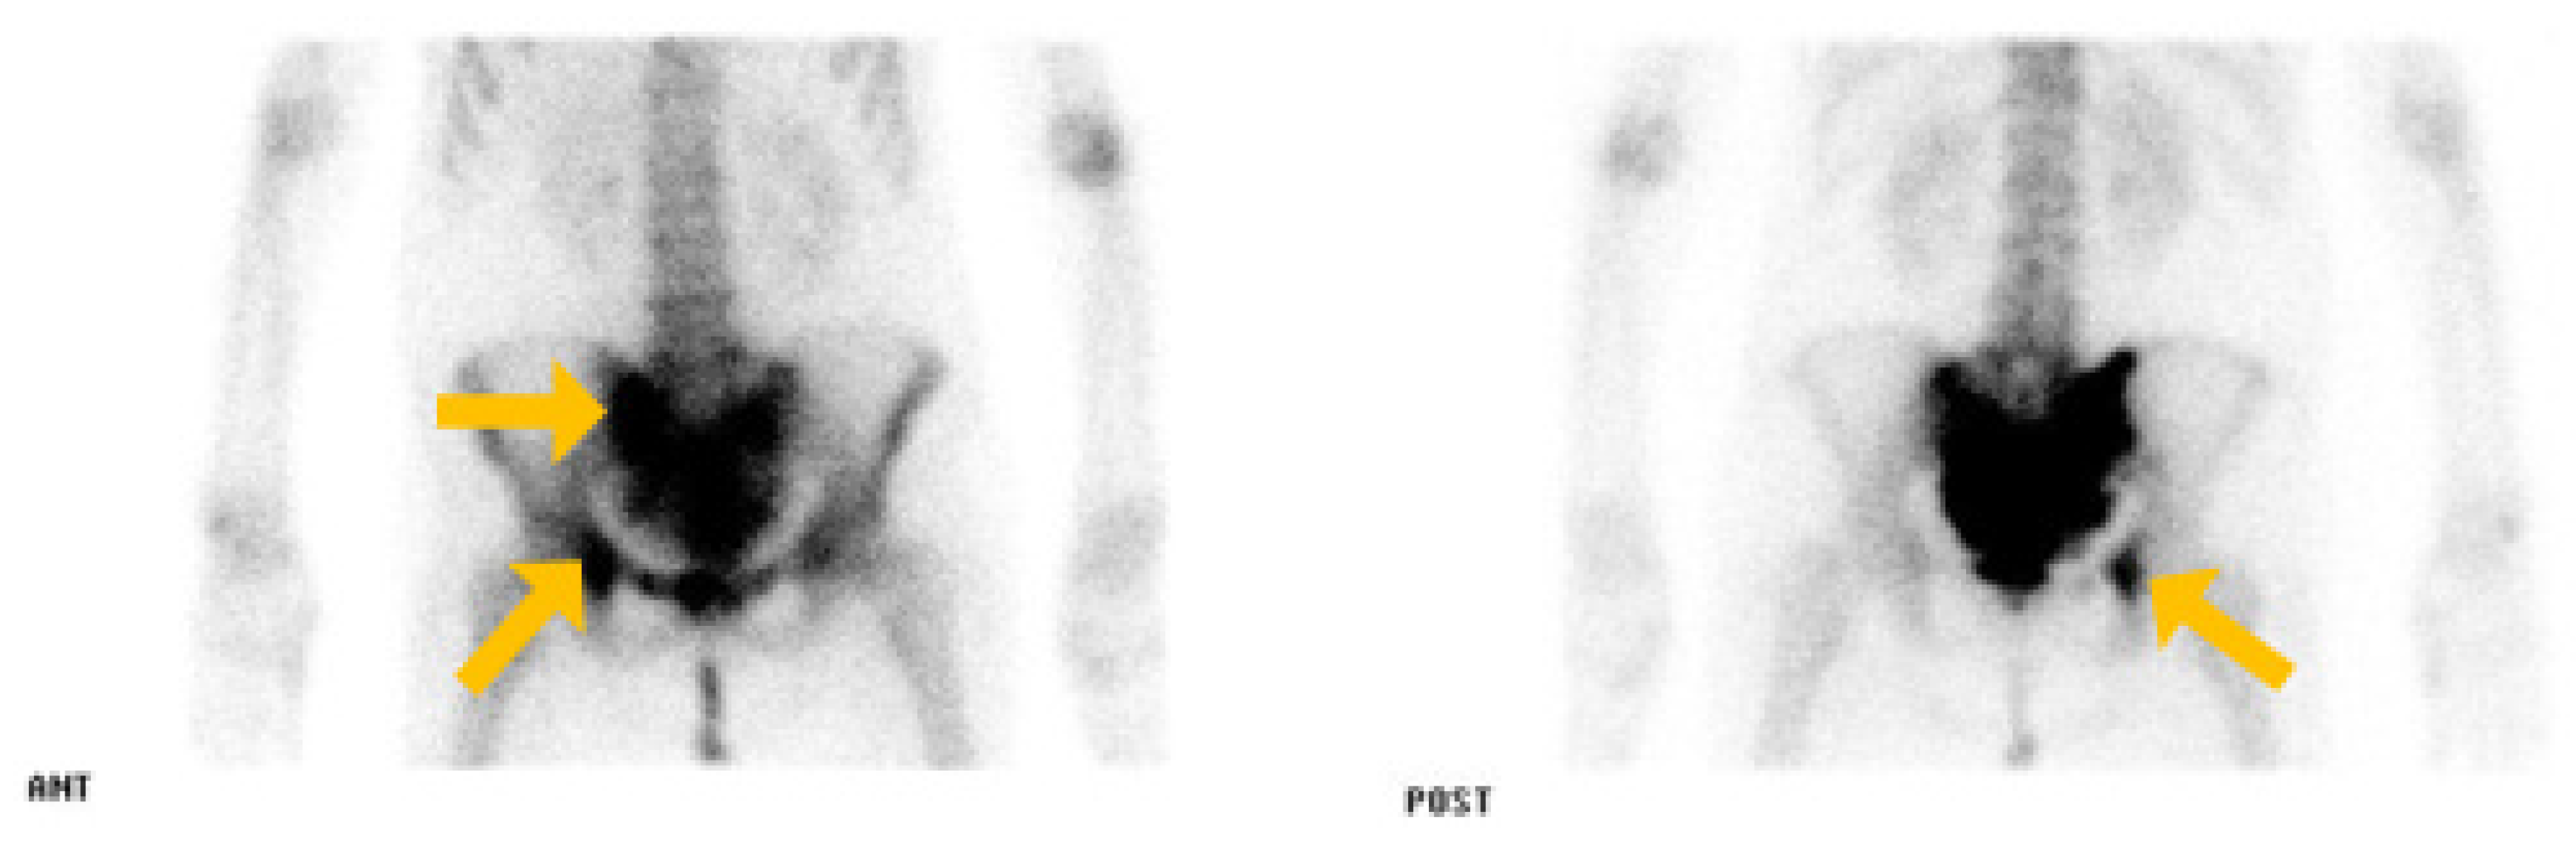

2. Case Report